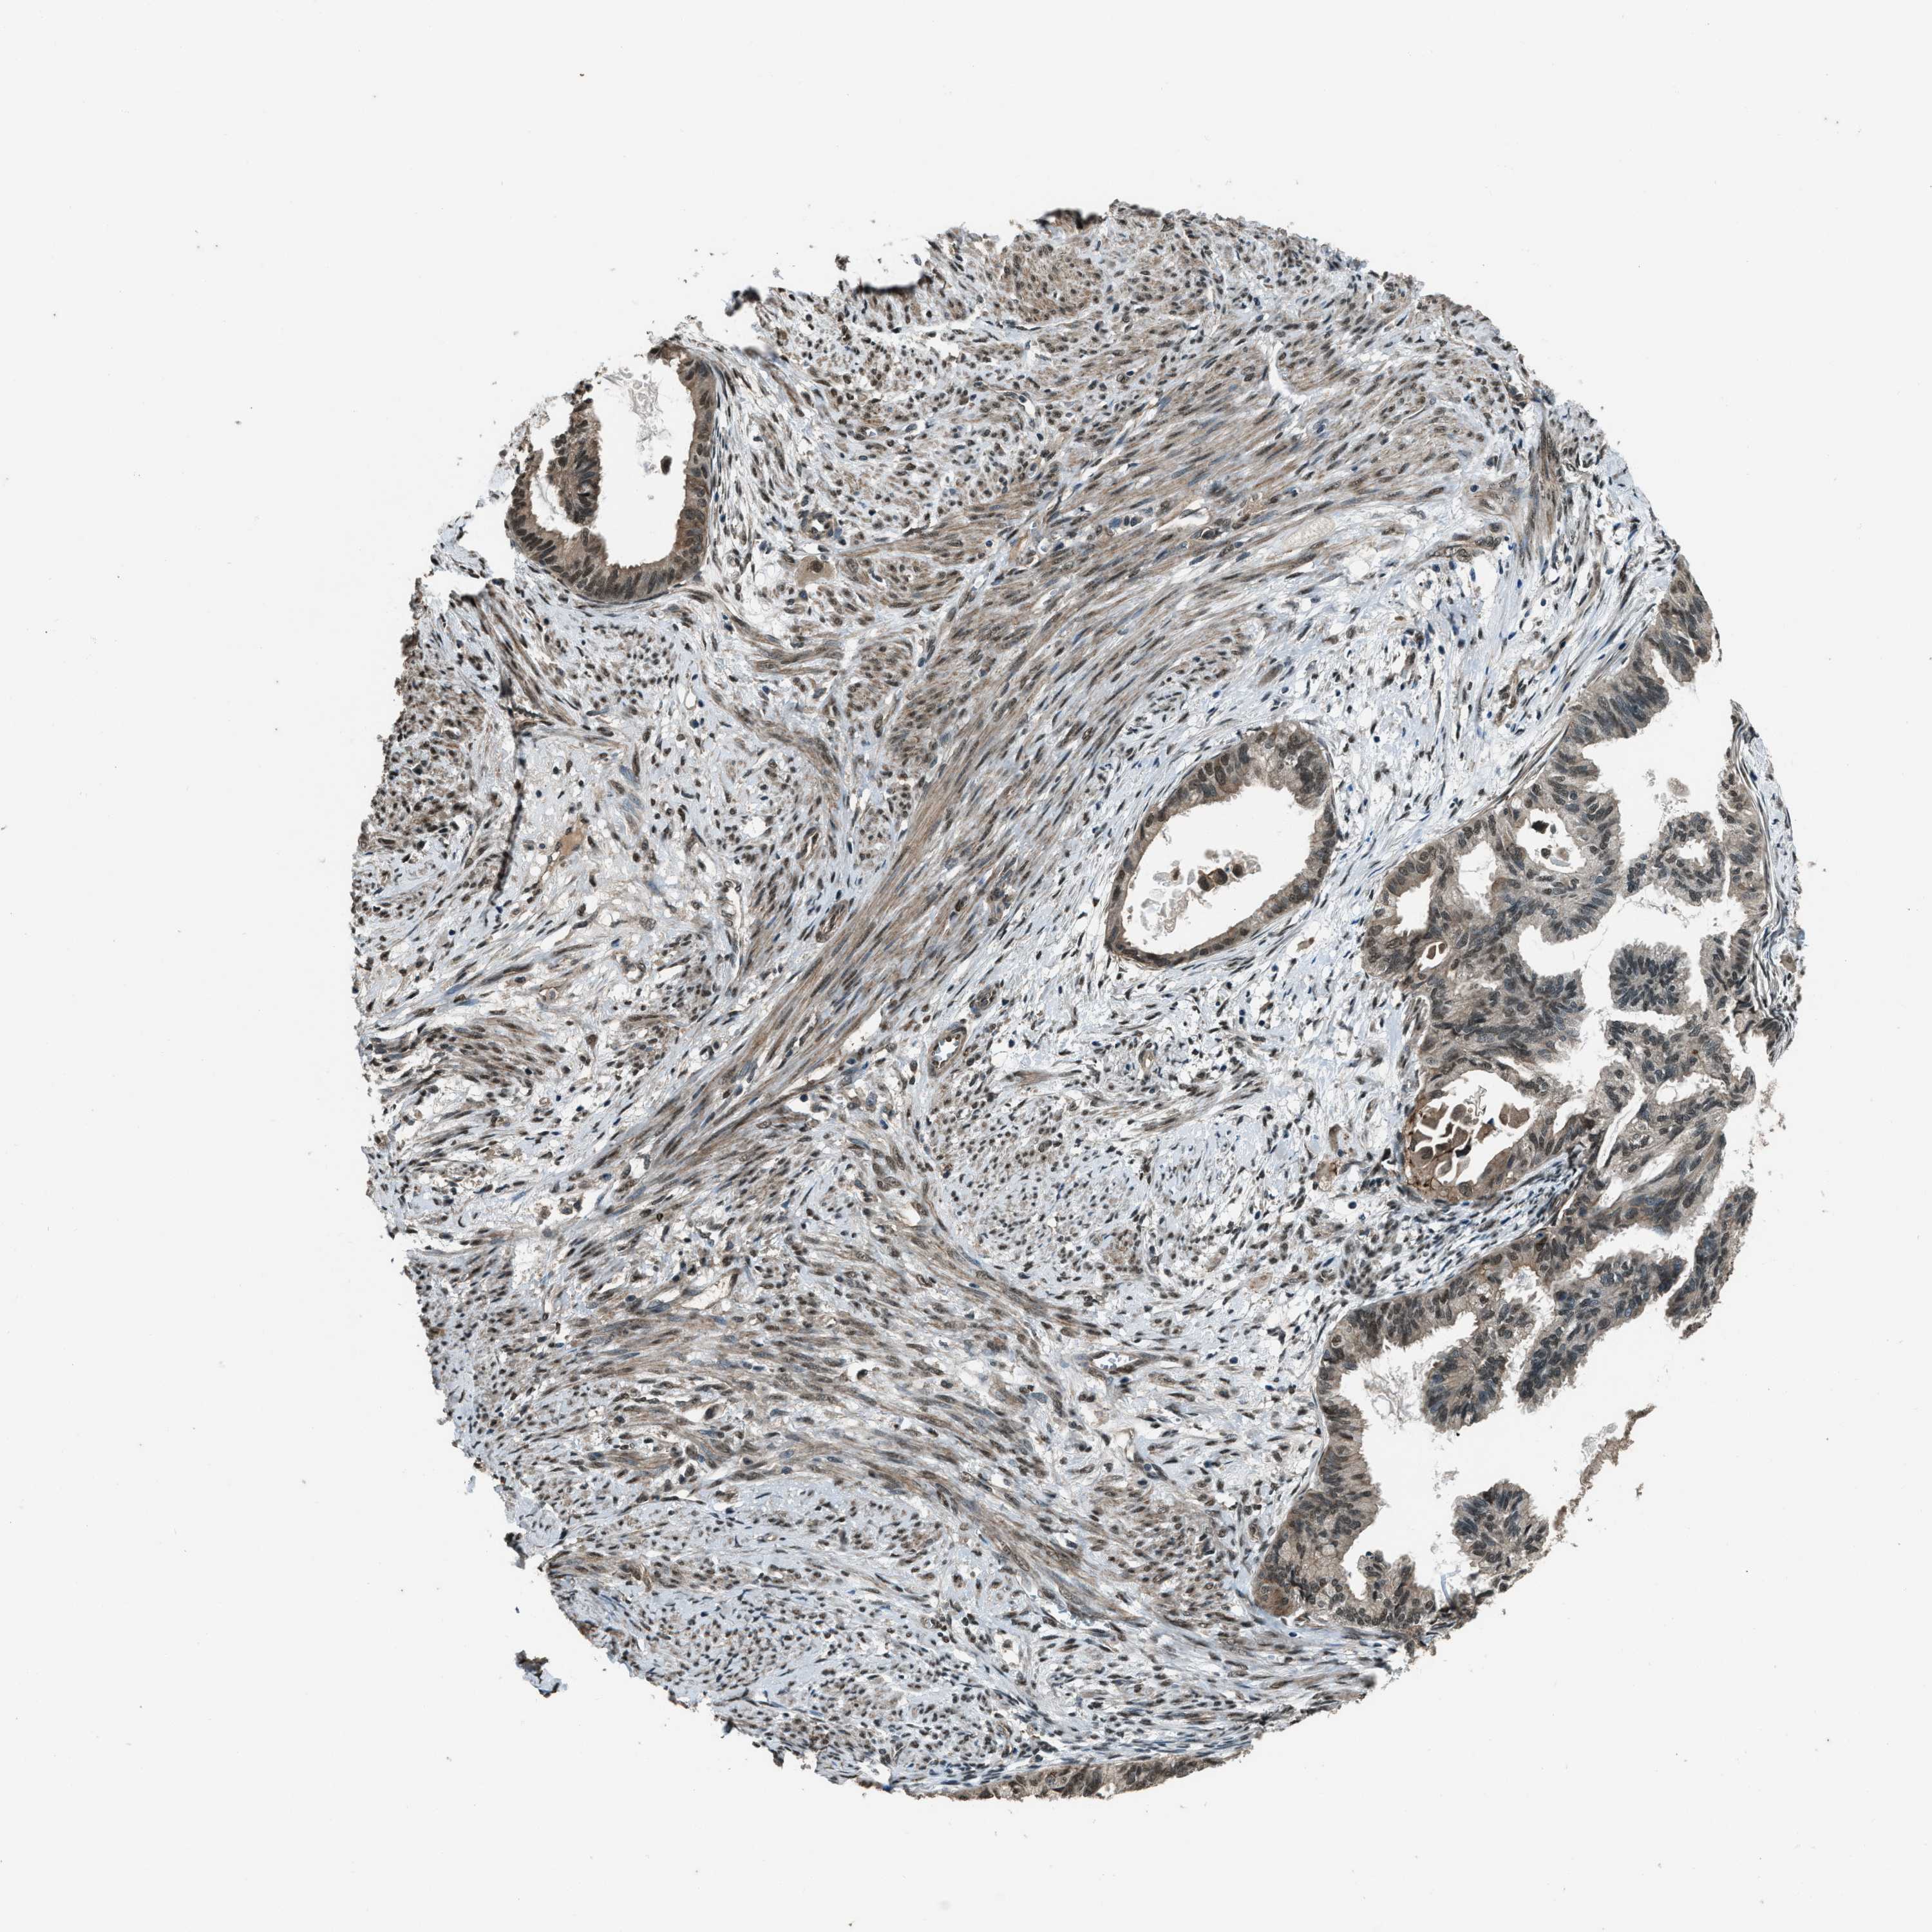

CERVICAL CANCER - Protein expressioni

A mouse-over function shows sample information and annotation data. Click on an image to view it in a full screen mode. Samples can be filtered based on level of antibody staining by selecting one or several of the following categories: high, medium, low and not detected. The assay and annotation is described here.

Note that samples used for immunohistochemistry by the Human Protein Atlas do not correspond to samples in the TCGA dataset.

Antibody stainingi

Antibody staining in the annotated cell types in the current human tissue is reported as not detected, low, medium, or high, based on conventional immunohistochemistry profiling in selected tissues. This score is based on the combination of the staining intensity and fraction of stained cells.

Each image is clickable and will lead to virtual microscopy that enables deeper exploration of all samples and also displays staining intensity scores, fraction scores and subcellular localization as well as patient and tissue information for each sample.

Antibody HPA020095

Antibody HPA020138

Antibody CAB010878

Antibody CAB080402

Squamous cell carcinoma, NOS